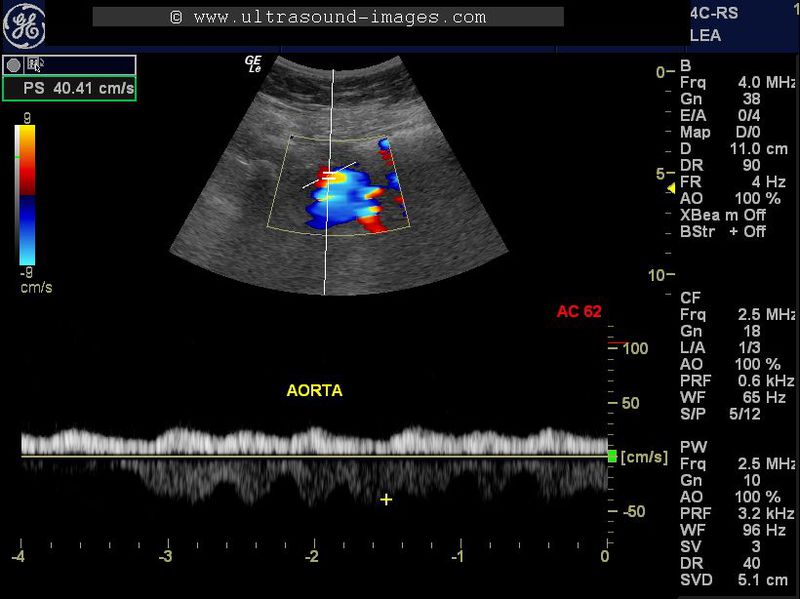

This elderly lady had pain in the right lower limb of acute onset. In addition, she had a history of atrial fibrillation the day before. Colour Doppler and spectral Doppler ultrasound imaging of both lower limbs and the aorta were done. This revealed marked dampening of flow in the arteries of the right lower limb as well as the left lower limb. The arteries we observed in this study included the femoral, popliteal and posterior tibial arteries. Evaluation of the lower abdominal aorta also showed a similar picture on spectral Doppler ultrasound. The colour Doppler and spectral Doppler ultrasound images shown above reveal a tardus-parvus flow pattern similar to that seen in veins. The PSV or peak systolic velocity was also extremely low throughout the right lower limb arteries as well as the left lower limb and the abdominal aorta. All these colour Doppler ultrasound findings point to an obstruction to the flow of blood somewhere along the abdominal aorta. This was confirmed on CT scan and MR imaging. The final diagnosis in this case was abdominal aortic thrombosis.